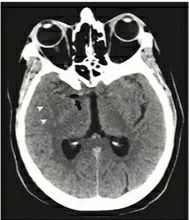

急诊行头部CT提示右侧大脑中动脉低密度(见下图):

急性脑梗死,应该是大脑中动脉高密度征,为何该患者是低密度呢?急诊科医生很是诧异,迅速请了神经内科会诊。

患者被送入神经科ICU病房,次日就出现了恶性大脑中综合征(见下图),去骨瓣减压后留住一命,但却终身残疾。